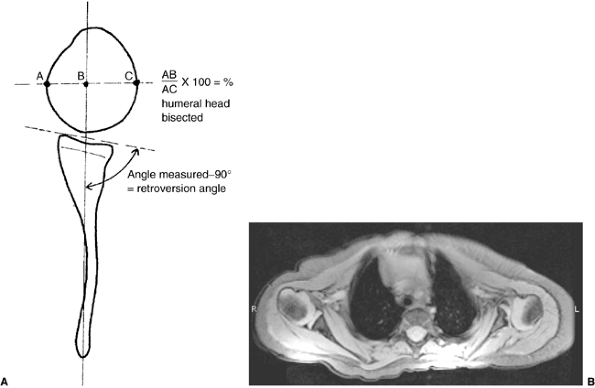

Figure 23.6 A:

Schematic showing the method of measuring the glenoscapular angle (glenoid vision) and the percentage of posterior subluxation of the humeral head. To measure the glenoscapular angle, a line is drawn parallel to the scapula and a second line is drawn tangential to the joint. The second line connects the anterior and posterior margins of the glenoid.The cartilaginous margins are used on magnetic resonance images. The osseous margins are used on computed tomographic scans. The intersecting line connects the center point of the first line (approximately the middle of the glenoid fossa) and the medial aspect of the scapula. The angle in the posterior medial quadrant is measured with a goniometer (arrow), and 90 degrees is then subtracted from this measurement to determine the glenoid version. The percentage of posterior subluxation is measured by defining the percentage of the humeral head that is anterior to the same scapular line. The greatest circumference of the head is measured as the distance from the scapular line to the anterior portion of the head. This ratio [the distance to the anterior aspect of the humeral head (AB) divided by the circumference of the humeral head (AC), multiplied by 100] is the percentage of subluxation. B: Magnetic resonance imaging of a type IV deformity with posterior humeral head subluxation and the development of a false glenoid. The glenoid is markedly retroverted. The contralateral glenohumeral joint is normal for age. |